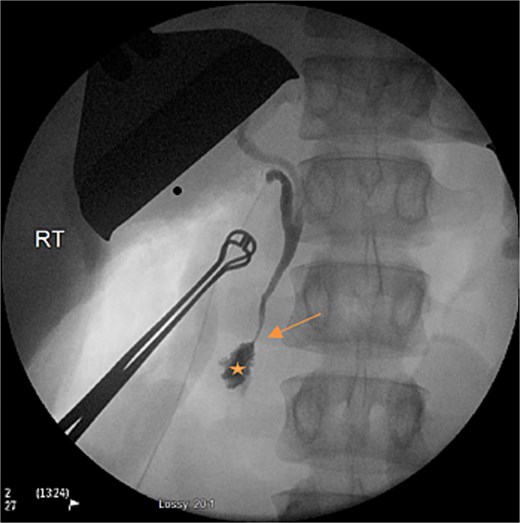

Second-look laparotomy was performed 12-hours following the index operation. A cholecystectomy was performed and jejunal continuity was re-established. Intraoperative cholangiogram was performed (Fig. 1), which showed no contrast flowing into the main pancreatic duct. Drains were placed and the abdomen was again temporarily closed.

Intraoperative cholangiogram on second-look laparotomy demonstrating the lack of filling of the main pancreatic duct (arrow), prior to contrast entering the duodenum (star).